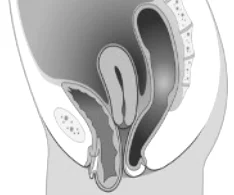

Cystokéla

Prolaps uteru

Rektokéla